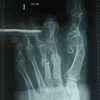

RESULTADOS

Caso 1: Hallux Valgus del Adulto